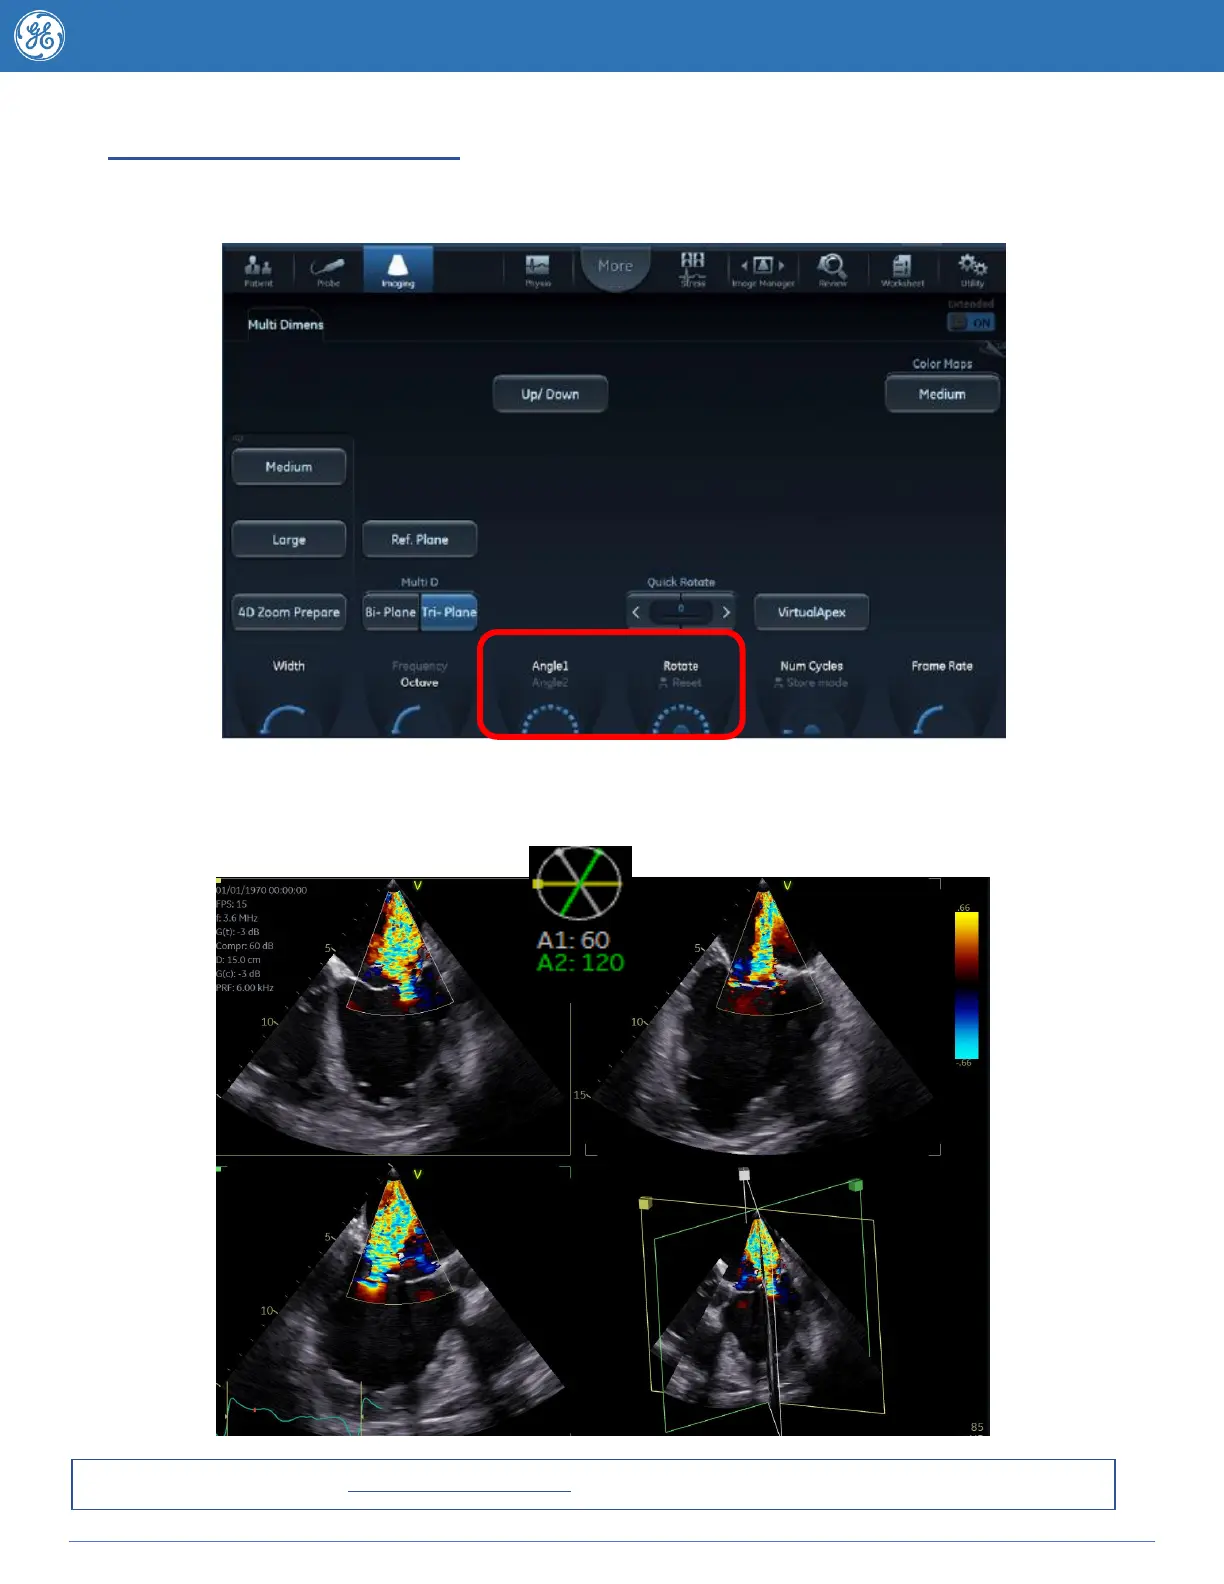

Multi D - Triplane Features

Change to Triplane on the touch screen (default is to Biplane)

Move probe as needed so that you can clearly see all three views.

In Tri-Plane the third scan plane (A2 or Angle 2) is represented by a green line - to change the angle of

the third image press the Angle 1rotary knob so that Angle 2is highlighted turning this knob will

rotate the third image individually.